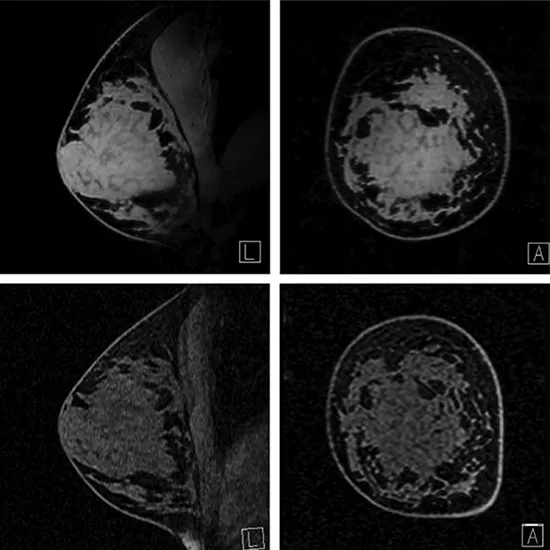

Mammography is a test used to detect breast cancer and other abnormalities in the breast. An MR spectroscopy graph shows the different chemical peaks of a suspected brain tumour.

On a padded scanning table, you lie on your stomach. Your breasts are positioned in a hollow depression in the table, which houses coils that detect magnetic signals. The table slides into the MRI machine's large opening.